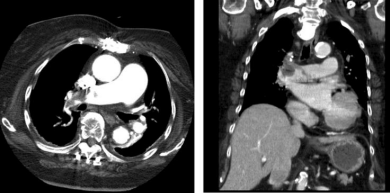

19. 一位82歲男性病患因骨頭壓痛,喘與腳腫至門診就診,血壓為96/60毫米汞柱,心跳每分鐘為80次,身體檢查呈現:結膜蒼白,頸靜脈怒張,兩側呼吸音減弱,心臟聽診左下胸骨呈現第三級收縮期雜音,並隨吸氣加重,心尖部呈現第三級收縮期雜音,兩側下肢明顯水腫。抽血檢查呈現BUN 70 mg/dl, cre 5.5mg/dl, Na 140 mmol/L, K 4.2 mmol/L, calcium 2.8 mmol/L, phosphate 5.3 mg/dL, Hb 10.7 g/dl, MCV 85.2 fL, WBC 9.61 k/uL, platelet 197 k/uL, albumin 3.1 g/dl, total protein 7.6 g/dl, 驗尿尿蛋白呈現3+, 頭骨X光呈現 punched-out病灶.骨髓切片檢查呈現明顯plasma cell neoplasm.醫師懷疑心臟也有被此疾病波及.請問下列心臟檢查結果,何者與這個懷疑較不吻合? (A) 心電圖A (B) 心電圖B (C) 心臟超音波呈現心肌肥厚與sparkling (D) 心臟超音波左心室出現restrictive filling pattern (E) 心臟超音波呈現中至重度三尖瓣膜閉鎖不全

圖 B